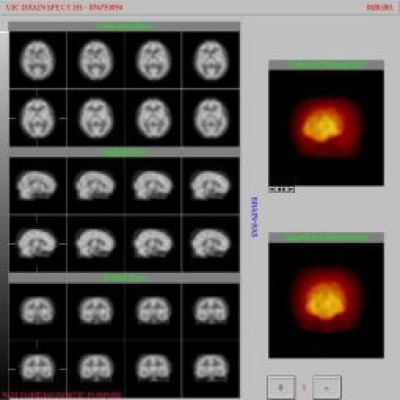

Muerte cerebral vista plana